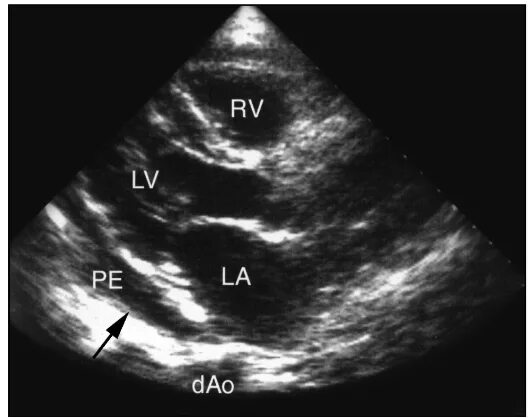

Уплотнение стенок аорты сердца на узи что